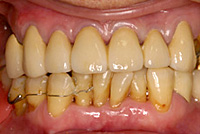

歯石除去前 |

歯石除去後 |

歯石除去前

歯石除去後